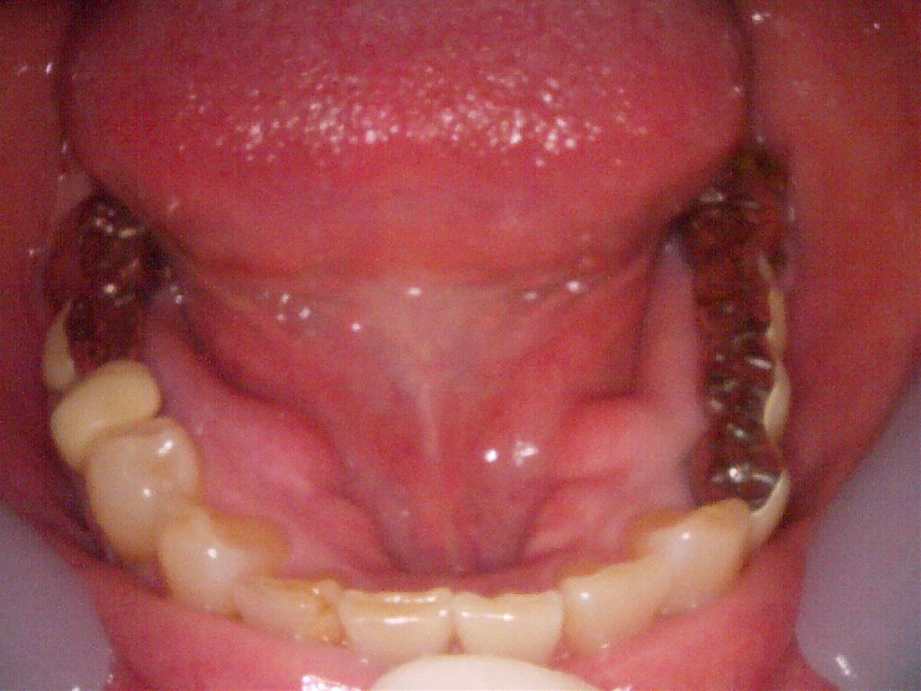

治療前

-

治療後

レントゲン写真

- 治療名称

- 右下6番欠損によるインプラント治療

- 患者の症状

- 20年前に抜歯してからそのままなのでどうにかしたい。

- 治療内容

- まず、CT撮影による精密な骨の分析・治療計画を立てガイドを使いインプラント埋入しインプラントが骨と結合するのを待つ間に仮の歯を入れます。その後本歯を作成して装着しました。

- 治療期間・回数

- インプラント埋入からジルコニアセットまで二か月半

- 費用

※自由診療となります - ■総額¥330,000(税込み) ■内訳:埋入(ガイド込み)¥200,000、仮歯¥20,000、被せ物(ジルコニア)¥80,000

- リスク・副作用

- ・術後の腫れ・痛み・出血 ・感染(インプラント周囲炎) ・インプラントの脱落 ・神経損傷によるしびれ ・破損・ゆるみ